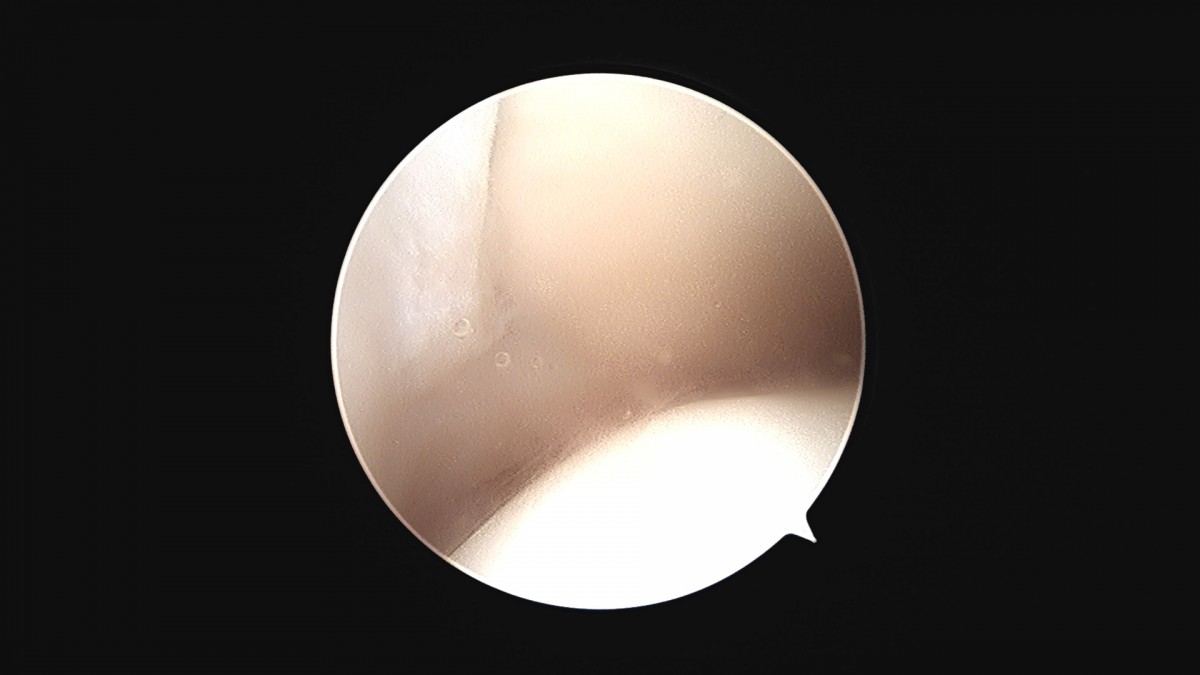

이재상원장님 발목 활액막 절제술 및 인대 봉합술 신진O 환자

dae765e4d9ac96aee867c9d6292d8784_1758003732_4452.jpg